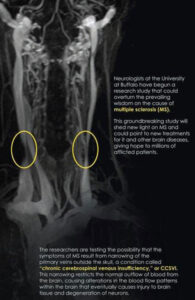

La ricerca, che coinvolge altri 40 centri in tutta Italia, ha infatti lo scopo di verificare l’associazione tra la CCSVI (insufficienza venosa cerebro-spinale cronica), ovvero un’occlusione parziale o totale del reflusso venoso dalla testa, e la sclerosi multipla . La sede di Reggio Emilia coinvolta è il Centro Studi Sclerosi Multipla dell’Arcispedale Santa Maria Nuova.

Quello tra la CCSVI e la sclerosi multipla è un legame ipotizzato per la prima volta dal chirurgo vascolare Paolo Zamboni dell’Università di Ferrara, al centro del dibattito medico, scientifico e mediatico da oltre un anno per aver proposto di intervenire chirurgicamente (tramite angioplastica) per correggere il difetto vascolare per migliorare anche il quadro clinico delle persone con sclerosi multipla.